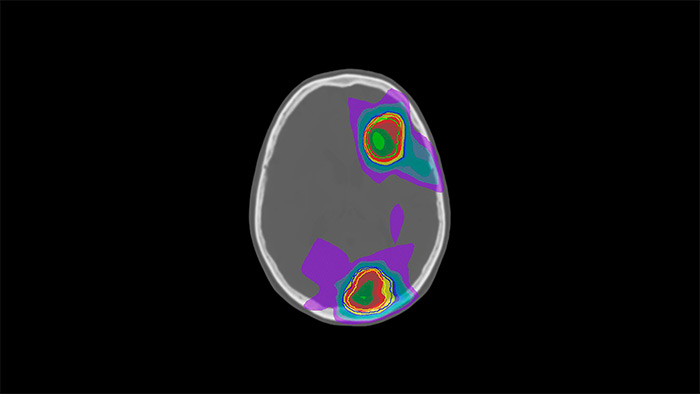

MRCAT Brain